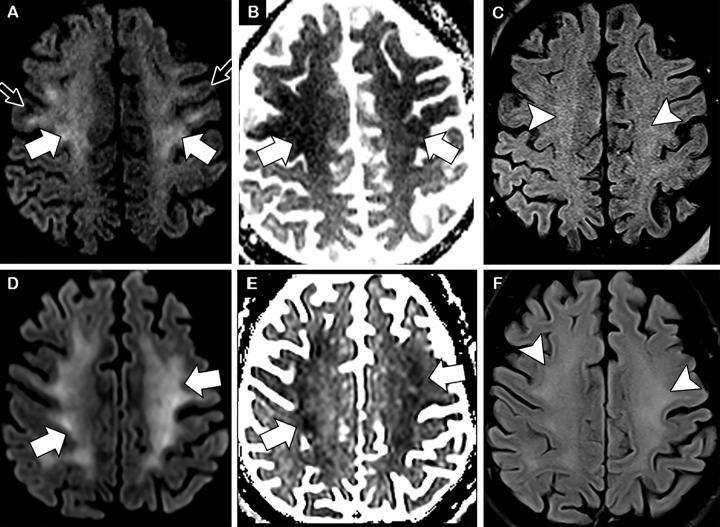

Diffuse leukoencephalopathy and juxtacortical and/or callosal microhemorrhages were brain imaging features in critically ill patients with coronavirus disease 2019. Coronavirus disease 2019 (COVID-19) has been reported in association with a variety of brain imaging findings such as ischemic infarct, hemorrhage, and acute hemorrhagic necrotizing encephalopathy. Herein, the authors report brain imaging features in 11 critically ill patients with COVID-19 with persistently diminished mental status who underwent MRI between April 5 and April 25, 2020. These imaging features include confluent T2 hyperintensity and mild restricted diffusion in bilateral supratentorial deep and subcortical white matter (in 10 of 11 patients) and multiple punctate microhemorrhages in juxtacortical and callosal white matter (in seven of 11 patients). The authors also discuss potential pathogeneses.

弥漫性脑白质病和皮质下及/或胼胝体微出血是 COVID-19 危重症患者的脑部影像学特征。有报道称,COVID-19(新冠肺炎)与多种脑部影像学表现相关,如缺血性梗死、出血和急性出血性坏死性脑病。在此,作者报告了 11 例 COVID-19 危重症患者的脑部影像学特征,这些患者的精神状态持续减退,于 2020 年 4 月 5 日至 4 月 25 日期间接受 MRI 检查。这些影像学特征包括 11 例患者中有 10 例双侧大脑半球深部和皮质下白质存在融合性 T2 高信号和轻度弥散受限,以及 7 例患者存在皮质下和胼胝体白质内多发性点状微出血。作者还讨论了潜在的发病机制。